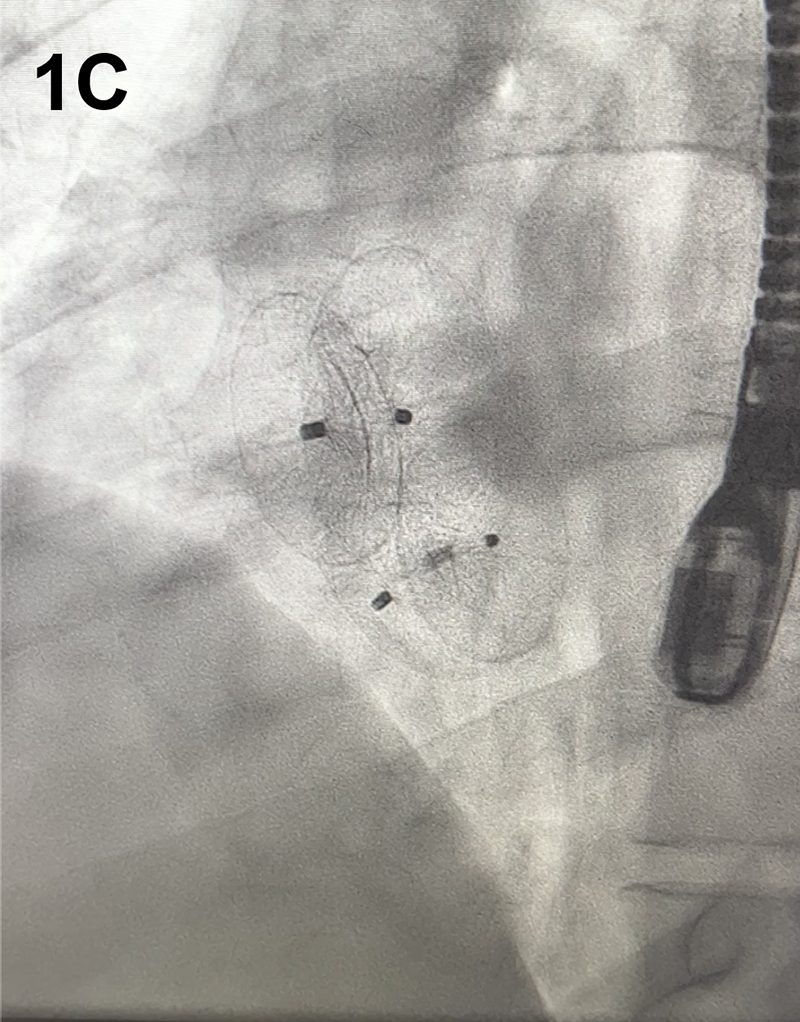

A 41-year-old man with no significant past medical history presented with a cryptogenic cerebrovascular accident (CVA). Brain magnetic resonance imaging (MRI) revealed small, multiple infarcts in the left frontoparietal white matter. Transthoracic echocardiography (TTE) demonstrated right heart enlargement, a large patent foramen ovale (PFO) with an atrial septal aneurysm (ASA) and high-risk features for paradoxical embolism. Planned percutaneous PFO closure was modified intra-procedurally when transesophageal echocardiography (TEE) revealed two distinct ostium secundum ASDs (Figure 1A–B). Right and left atrial pressures measured 10 mmHg and 18 mmHg, respectively. The 21 mm and 8 mm defects were consistent with a large fenestrated ASD with predominant left-to-right shunting. Dual-device closure was pursued to ensure complete occlusion. A 24 mm Amplatzer septal occluder (ASO) was deployed for the larger defect, and a 30 mm cribriform ASO for the smaller defect (Figure 1C–D). TEE confirmed stable device positioning and complete closure with no residual shunting. The patient tolerated the procedure well with no complications.

Figure 1. (A–D) Two-dimensional transesophageal echocardiography (TEE) with color Doppler demonstrates two distinct atrial septal defects with left-to-right shunting (A). TEE confirms successful closure of both defects following implantation of dual Amplatzer septal occluder devices (C). Fluoroscopic imaging during the procedure shows the positioning of both occluder devices (D).

For defect sizing, a 24 mm Amplatzer sizing balloon was inflated across the interatrial septum. This revealed a primary defect measuring 21 mm. Additionally, a separate 8 mm ostium secundum ASD was identified. A 24 mm Amplatzer ASO was delivered via a 10F Torquevue sheath and deployed under TEE and fluoroscopic guidance. The second defect was crossed using a 6F multipurpose catheter, and a 30 mm cribriform ASO was deployed using the same technique, overlapping with the first device. Final imaging confirmed complete closure of both defects with no residual shunting.